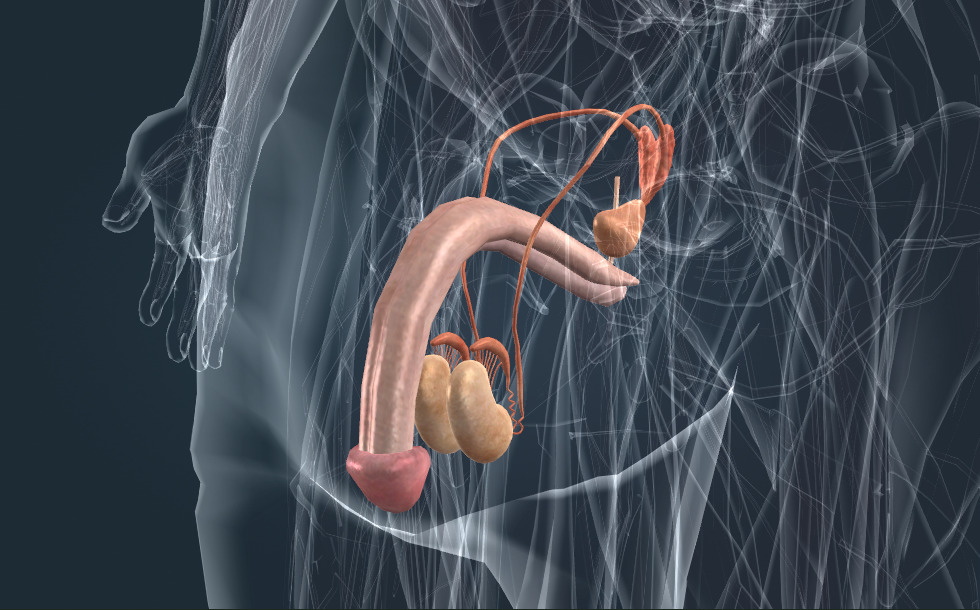

Sistema reproductivo

- testículo - Produce semen y testosterona (hormona sexual masculina) que estimula la maduración del semen y el desarrollo de un físico varonil y del vello androgénico.

- epidídimo - Almacena el semen producido en los testículos.

- conducto deferente

- vesícula seminal - Juega un importante papel en la formación del semen.

- próstata - Juega un importante papel en la formación del semen.

Los genitales sirven para la reproducción, producen gametos. Durante la fertilización, el ovocito se une con un espermatozoide y forman juntos un cigoto a partir del cual se desarrolla el embrión. Las glándulas reproductoras masculinas son los testículos, que producen semen. Este se almacena en el epidídimo y durante la eyaculación sale por la uretra. El semen se produce en la próstata y las vesículas seminales.

Los genitales sirven para la reproducción, producen gametos. Durante la fertilización, el ovocito se une con un espermatozoide y forman juntos un cigoto a partir del cual se desarrolla el embrión. Las glándulas reproductoras masculinas son los testículos, que producen semen. Este se almacena en el epidídimo y durante la eyaculación sale por la uretra. El semen se produce en la próstata y las vesículas seminales.